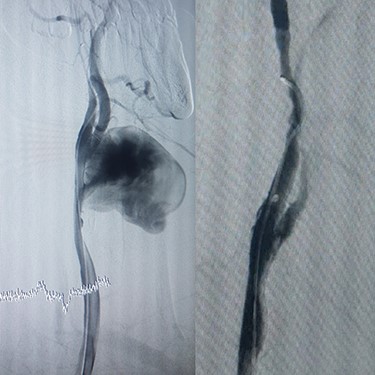

Case 1 — A 30-year-old man who was a known case of BD and was diagnosed 5 years prior to admission to our center. The patient was admitted to our hospital with progressive chest and left upper extremity pain for 4 months. Chest computed tomography (CT) scan revealed a left saccular subclavian aneurysm (Fig. 1A) with no sign of rupture or pleural effusion. After 48 hours of admission, he suffered from severe abdominal pain, hypotension and tachycardia. After resuscitation, thoracoabdominal CT angiogram (CTA) was conducted which showed an aneurysm of the thoracoabdominal aorta (Fig. 1B) and was ruptured near Celiac artery origin. Endoxan (1 gr) and Methyl prednisolon pulse (1 gr daily up to 3 days) were injected. Emergency thoracic endo vascular aortic repair (TEVAR) was performed and he became stable after the procedure. Tablet of Prednisolon 5 mg was prescribed twice daily. In follow-up angiography, the subclavian artery was ligated after the origin of the aortic arch and the aneurysm was thrombosed; however, since his arm was viable, conservative management was selected. After 1 year, he had no disabling abnormality on physical examination of his arm and no sign of endoleak was identified in the follow-up CTA.

(A) CTA of the left subclavian aneurysm (right), (B) CTA of thoraco abdomen aneurysm (left).